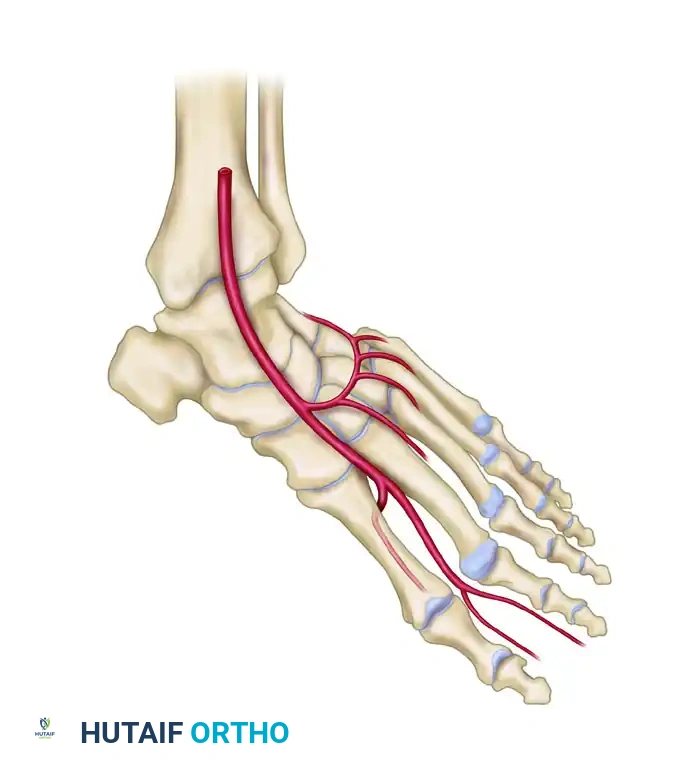

A masterful grasp of the dorsal foot vascular architecture is the foundation of a successful dorsalis pedis free flap. The primary arterial supply is the dorsalis pedis artery (DPA), a direct continuation of the anterior tibial artery as it passes deep to the extensor retinaculum.

As the DPA courses distally over the dorsal aspect of the tarsal bones, it gives off the lateral and medial tarsal arteries, followed by the arcuate artery.

Distal to the arcuate artery, the DPA bifurcates into two terminal branches:

1. First Dorsal Metatarsal Artery (FDMA): Courses distally within the first intermetatarsal space to supply the dorsal skin of the great and second toes.

2. Deep Plantar (Communicating) Artery: Plunges plantarly between the two heads of the first dorsal interosseous muscle to anastomose with the lateral plantar artery, completing the plantar arch.